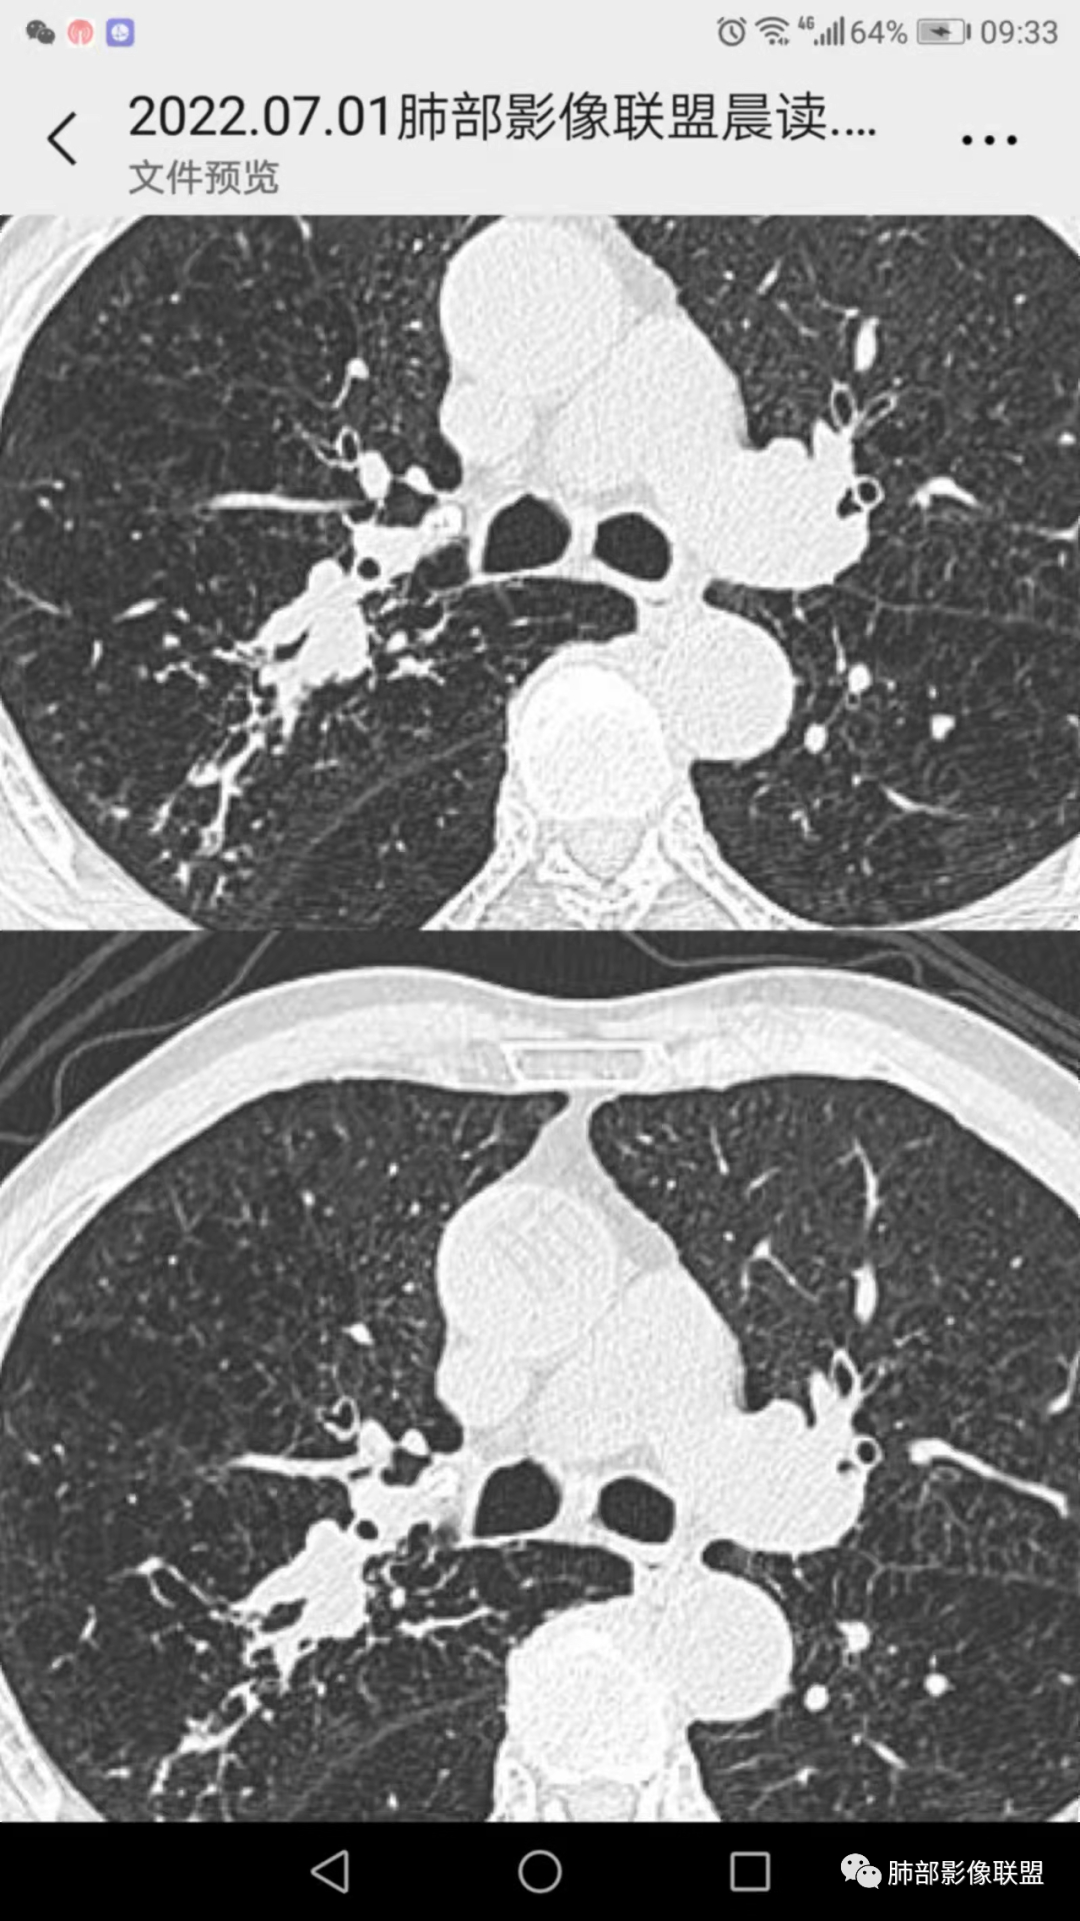

3、影像表现:肺气肿背景,右肺上叶后段支气管开口阻塞并见腔内软组织影轻度突向叶支气管,阻塞段以远支气管及分支扩张填塞呈指套样改变,轻度不均匀强化,外周点片影,符合阻塞性炎性表现,现有图像资料未见明确肺门纵膈淋巴结增大。

上图,鳞癌,腔内软组织占位,局部膨大,不均匀强化,伴远端粘液栓。

上图,小细胞肺癌,病灶从肺门朝外沿支气管爬行,呈指套样改变,病灶周围阻塞性肺炎较轻。